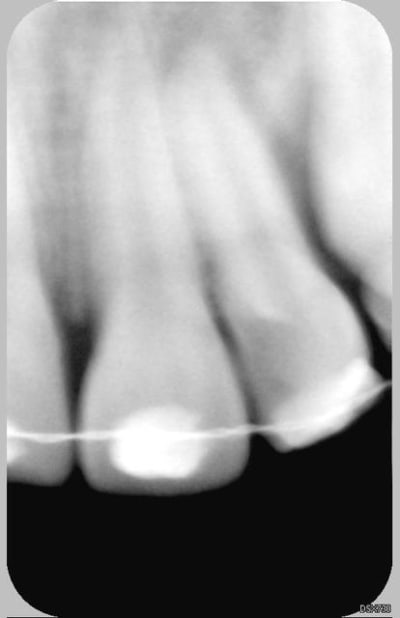

Patiente de 11 ans ayant la 21 expulsée début avril 2006. La dent a été repositionnée en centre de soins. Dans un premier temps, pas de perte de sensibilité. Puis dans un deuxième temps, comme un goût de ça tourne mal avec certainement rhyzalyse interne de la 22 (traitement thermafil pas d'école).

la on est dans un tres beau cas de resorption inflammatoire des 21 et 22

La 22 n'était pas cariée, simplement en rotation (elle l'est encore)avec une anatomie atypique (angle mésio-occlusal très fin).

Le milieu est extémement infecté et la résorbtion de la 21 n'est pas aseptique : donc je ne peux pas attendre.

Ci joint la première radio de ces dents avec attelles centre de soins universitaire